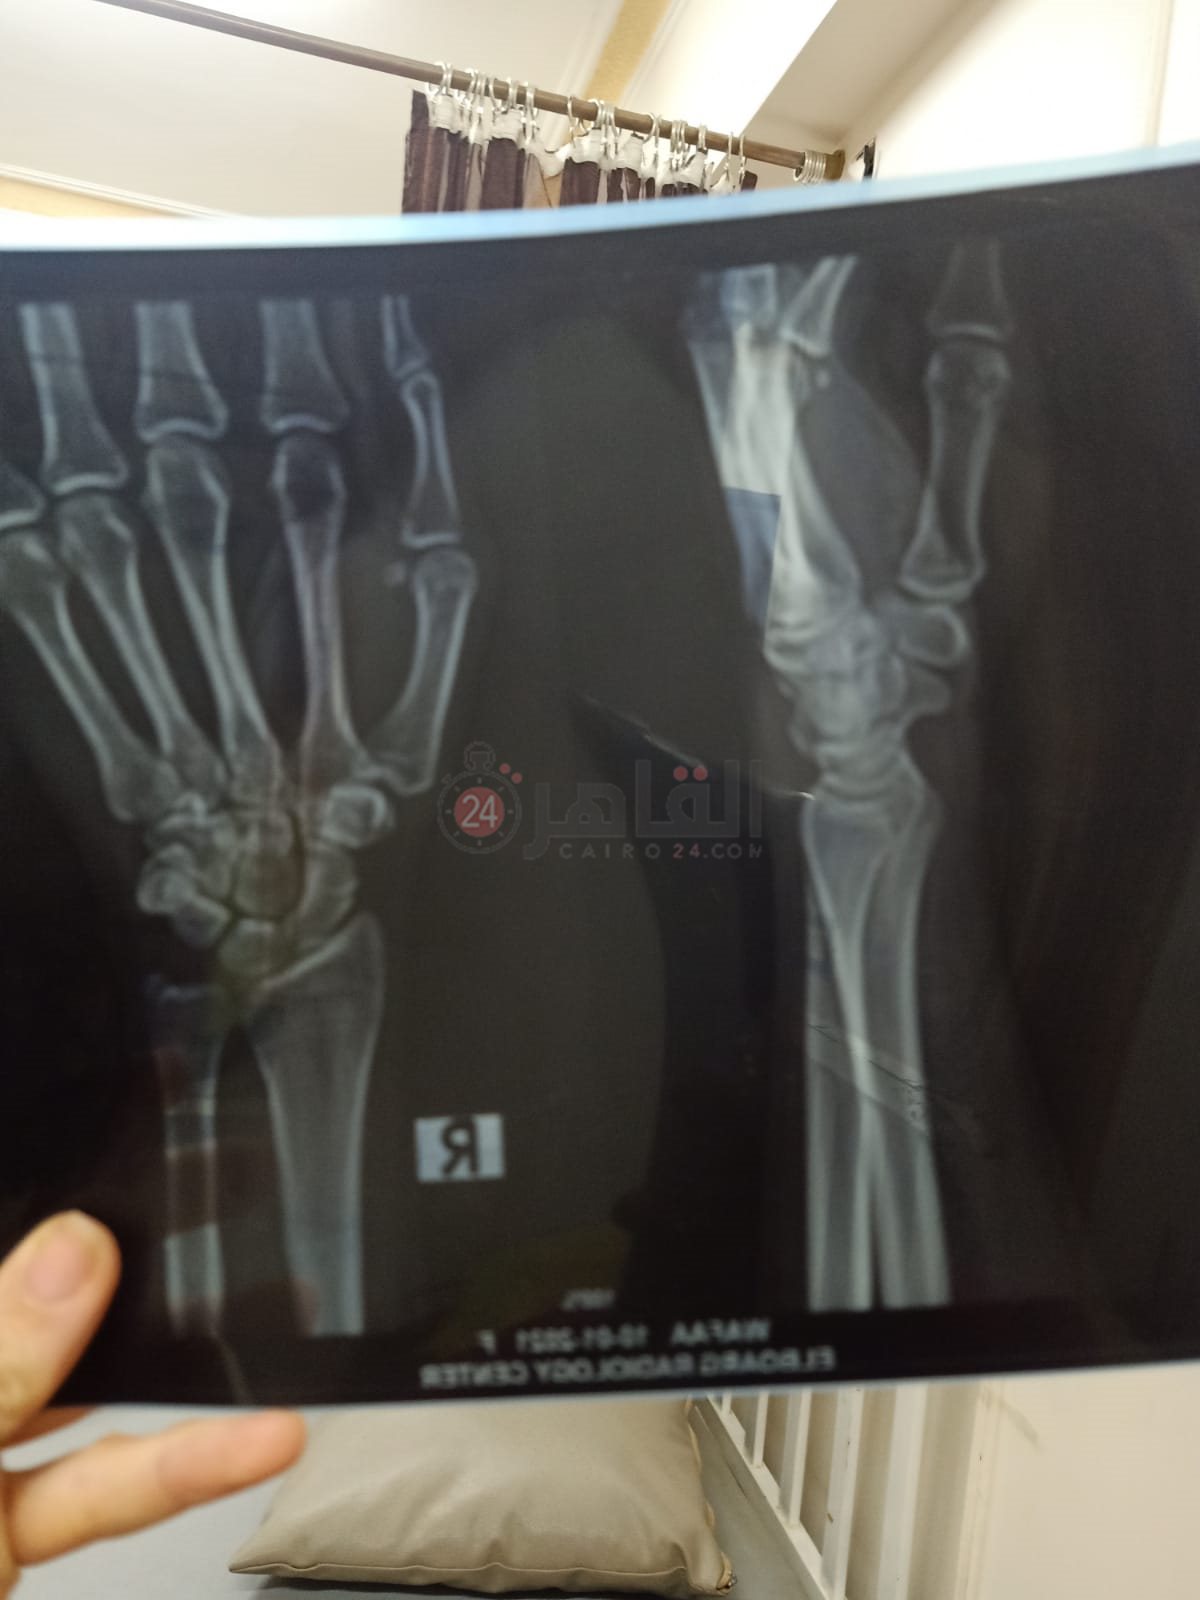

ريان طفل بالمنوفية يعاني من مرض العظم الزجاجي والذي يجعله عرضه لكسر العظام بشكل متكرر، صاحب الثلاث سنوات ونصف تعرض للكسر ما يزيد عن 51 مرة، في كل أطراف الجسم بالإضافة إلى خضوعه لعملية جراحية لتركيب مسمار مطاطي نخاعي في الذراع الأيمن ويحتاج لعملية جراحية أخرى لتركيب نفس المسمار في الذراع الأيسر خلال 15 يوما على الأكثر.

وتروي والدة ريان لـ القاهرة 24 مأساة ابنها صاحب الثلاث سنوات ونصف، والذي يتعرض للكسور بشكل متواصل، وتؤكد على حجم المعاناة التي تعرض لها الصغير حيث تعرض ذراعه الأيمن لـ 21 كسرا، والذراع الأيسر 18 كسرا وكل قدم من أقدامه 6 كسور بالإضافة إلى تجبيس كامل في القدمين بـ 5 بناطيل من الجبس.

وتؤكد والدة الطفل والذي يقيم بمدينة سرس الليان، أن والده يعمل صنايعي بأحد المحلات، وابنها يحتاج حقنة بـ 2500 جنيه شهريا، وخضع لعملية جراحية لتركيب مسمار مطاطي نخاعي في الذراع الأيمن بمبلغ 65 ألف جنيه ويحتاج لأخرى في اليد اليسرى بمبلغ 75 ألف جنيها وهي خارج إمكانية الأسرة في الوقت الحالي، وتناشد المسئولين التكفل بحالته التي تحتاج إلى استشاري عظام كبير حتى يتمكن من تركيب المسمار بشكل صحيح، حيث أن تلك العملية تحتاج لبراعة وخبرة.